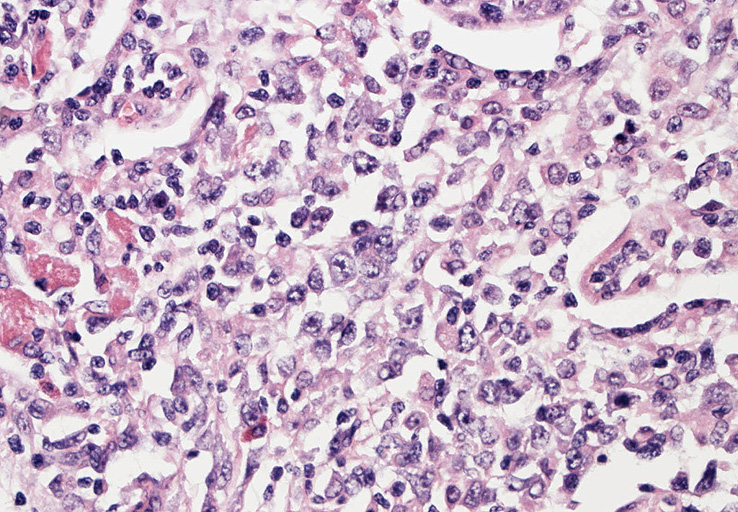

EBUS-GS(ガイドシース併用気管支腔内超音波断層法)による肺生検組織病理所見.

血管周囲性に大型類円形核や不整形核をもつ腫瘍細胞がシート状密に浸潤増殖している. Mitosisが多く認められる.細血管閉塞や破壊の所見がある.

間質にもシート状の腫瘍細胞浸潤がある. 大小 pleomorphicな傾向.(A, B). necrosisが認められる(C). 細気管支上皮直下まで密な浸潤あり, 小型リンパ球が混在している.(D)

血管中心性浸潤. 障害された血管内に血栓が形成されている.CD20陽性細胞がシート状密に浸潤, CD3陽性T細胞が多く混在している. EBER-ISH陽性 EBV感染細胞が多数認められ, >50 hpf, 定義より Grade3となる. 陽性細胞のサイズは大小さまざまであることに注意.